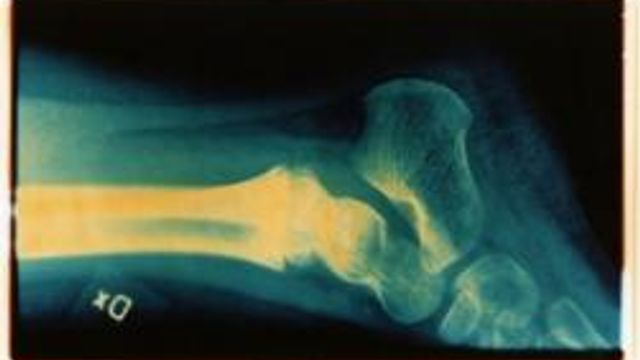

L'osteoporosi è principalmente un problema femminile, visto che colpisce nell'80 per cento dei casi le donne, ma non bisogna dimenticare che ne soffrono anche gli uomini che la trascurano di più. Se ne discute a Roma nel congresso internazionale Gender and Science al Policlinico Umberto I. Il convegno è organizzato dall'Università Sapienza di Roma con l'Università di Sassari ed è promosso dalla Fondazione internazionale Menarini.

Due facce della malattia - Andrea Lenzi, ordinario di endocrinologia alla Sapienza spiega: "Esistono due osteoporosi: una femminile e una maschile".

Il grasso addominale - Lenzi ha coordinato una ricerca condotta su 86 uomini in sovrappeso. L'esperto afferma: "Abbiamo osservato un'alta correlazione fra grasso accumulato all'addome e osteoporosi maschile. Una volta si diceva che il sovrappeso svolgesse un ruolo protettivo contro la debolezza ossea invece non è così. Inoltre, si sostiene che sia una patologia tipicamente femminile perché da ricondursi a un'involuzione ossea associata all'invecchiamento e al calo di ormoni estrogeni, ma ci sono molti altri fattori che concorrono a produrre fragilità ossea anche negli uomini".

Nell'uomo compare prima - Andrea Giustina, ordinario di endocrinologia all'Università di Brescia spiega: "La cosiddetta “osteoporosi secondaria” è più comune fra gli uomini. Mentre per le donne è legata alla menopausa, nell'uomo compare molti anni prima ma si riconosce solo quando si fratturano le ossa perché viene spesso trascurata".

Lo specialista conclude: "Abbiamo dimostrato che per gli uomini la patologia consegue soprattutto l'uso cronico di alcuni farmaci, come cortisone, alcune terapie per l'asma e per il tumore alla prostata. E' anche conseguente ad alcune patologie gastrointestinali comuni come la celiachia e ad alcune malattie endocrine maschili. Gli uomini sono cosi soggetti a fratture soprattutto nella zona delle anche e alle vertebre".